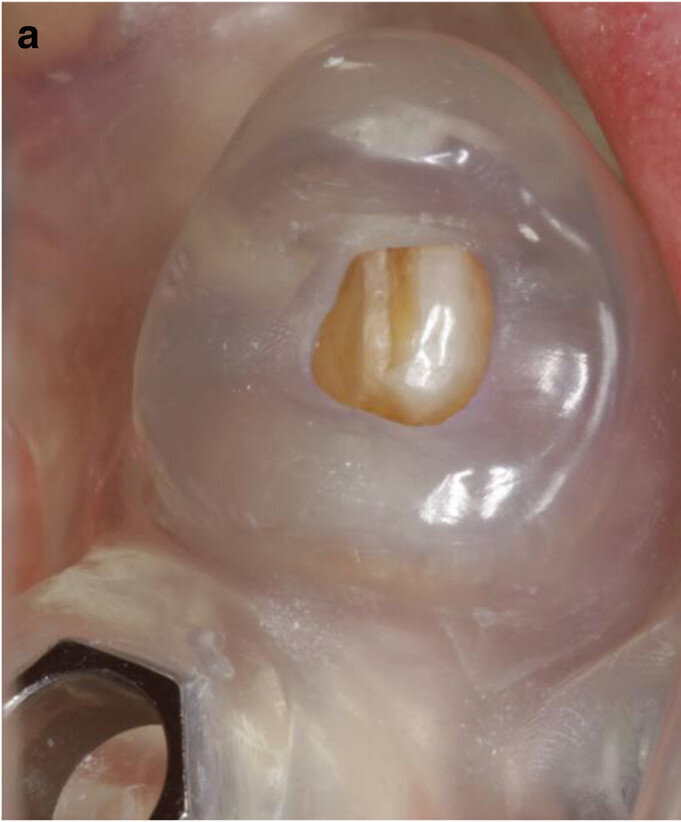

Fig. 8a: Close-up view of the first CAD/CAM guide in situ (tooth- and mucosa-supported) showing the perfect fit on tooth #33 (a). Occlusal view of the second CAD/CAM guide (implant- and mucosa-supported) after extraction of teeth #42 and 33 and placement of implants in positions #44 and 35 (b).

The two-step approach entailed the flapless, guided insertion of four posterior implants (ELEMENT RC, 4.5 × 9.5 mm; Thommen Medical), using the first surgical template, which was tooth- and mucosa-supported (Fig. 8a). The template was then removed and teeth #42 and 33, which had supported the guide, were extracted. Thereafter, the second surgical template was positioned and stabilised on the four posterior implants with the help of specific abutments and the same anchor pins (Fig. 8b), thus allowing guided placement of implants (ELEMENT RC, 4.5 × 9.5 mm) in positions #42 and 33 immediately after the extractions. All the implants were inserted at a torque of 35 Ncm and had good primary stability.